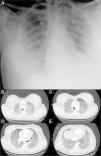

On admission patient had Glasgow Coma Scale Score of 15, tachypnea and tachycardia, with central cyanosis and was sweating. No fever. Blood pressure was 100/70mmHg and respiratory rate 40/min. Arterial blood gas analysis under 15l/min oxygen therapy by a non-rebreathing mask with reservoir showed global respiratory insufficiency and sever acidemia (pH 7.22, pO2 31mmHg, pCO2 49mmHg, HCO3− 17.6mEq/L, SatO2 55%, lactate 6.17mmol/L). Heart auscultation revealed audible S1 and S2 and chest auscultation revealed bilateral rales. The remaining physical examination just was unremarkable with exception of mild redness, warmth and swelling of the gluteus. No fluctuation was detected and no indication for surgical approach was considered. Chest X-ray showed bilateral lung infiltrates (Fig. 1A). At this time was intubated and mechanically ventilated.

Electrocardiogram showed sinus tachycardia with S1Q3T3 pattern. Computed tomography angiography ruled out pulmonary embolism and disclosed bilateral consolidations with air-bronchograms and ground-glass-appearing opacities suggestive of alveolar damage (Fig. 1B–E). Transthoracic echocardiogram revealed normal left ventricular systolic function with no contractility alterations, valve dysfunctions or pericardial effusion.